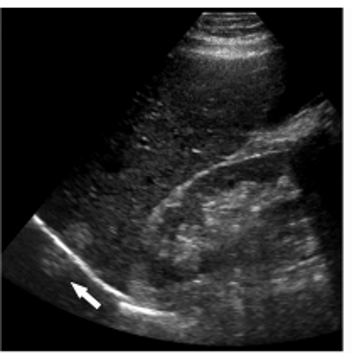

The artifact shown is reverberation caused by back and forth reflection of the ultrasound beam between 2 closely spaced interfaces. These reverberation echoes appear as multiple equally spaced lines, which decrease in intensity with increasing depth. This artifact is often caused by highly reflective interfaces, e.g., metallic objects or calcification in tissues.

reverberation artifact:

multiple equidistance echoes